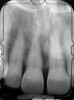

The 9-year postoperative radiograph.

Fig. 7

Then, too, are opportunities to prepare the site for regeneration by coupling therapies, applying an enamel matrix derivative, along with traditional bone grafts of demineralized freeze-dried bone allograft; potentially, gains in attachment with minimal probing depth and retained papilla may avoid the need for an implant (Figure 2 through Figure 7).

In the coming decades, restorative treatment for aging patients who experience facial growth with recession and erosion below the cemento-enamel junction because of tooth movement may be especially challenging. However, if dentists can employ the tenets of regeneration using autogenous tissues or a cellular dermal matrix combined with enamel matrix derivatives as a regulatory protein, they may predictably achieve large amounts of root coverage with thickened periodontium. This would not eliminate the need for restorative dentistry, but would enable restorative dentists to place restorations that are supragingival and are easily accessible for the patient and the therapist during maintenance (Figure 8 through Figure 10).